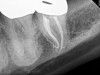

Fig 9. It is clinically acceptable to have results with the sealer puff (Figure 9) and without (Figure 10).

Figure 9

Fig 10. It is clinically acceptable to have results with the sealer puff (Figure 9) and without (Figure 10).

Figure 10